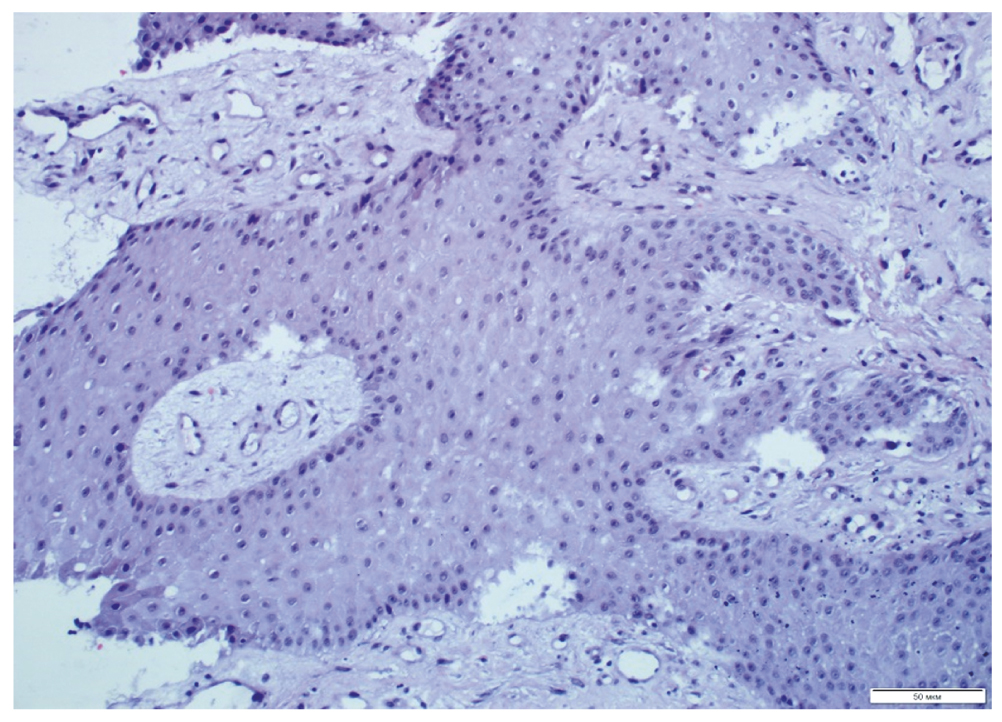

На 14-е сутки в основной группе в ходе микроскопии установлены признаки активации РП. В зоне фибриноидно-некротических изменений выявлен неоангиогенез в виде фрагментов грануляционной ткани; просматривались элементы полиморфно-ядерных лейкоцитов межуточной ткани (рис. 3).

Рис. 3. Биоптат ткани дна пролежня на 14-е сутки лечения с использованием высокочастотной электростимуляции. Окраска гематоксилином и эозином.

Fig. 3. Biopsy of the bottom of the bedsore on the 14th day of treatment using high-frequency electrical stimulation. Stained with hematoxylin and eosin.

В группе сравнения гистологическая картина очага за те же сроки практически не изменилась. Пролиферация фибробластов была выражена крайне слабо, а фибриноидно-некротические изменения сохранялись и были сравнимы с исходными.